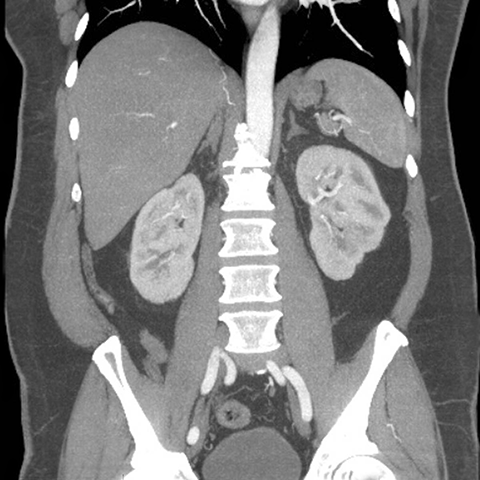

Abdominal Wall Muscles Normal Anatomy, Coronal CT [9 of 9]